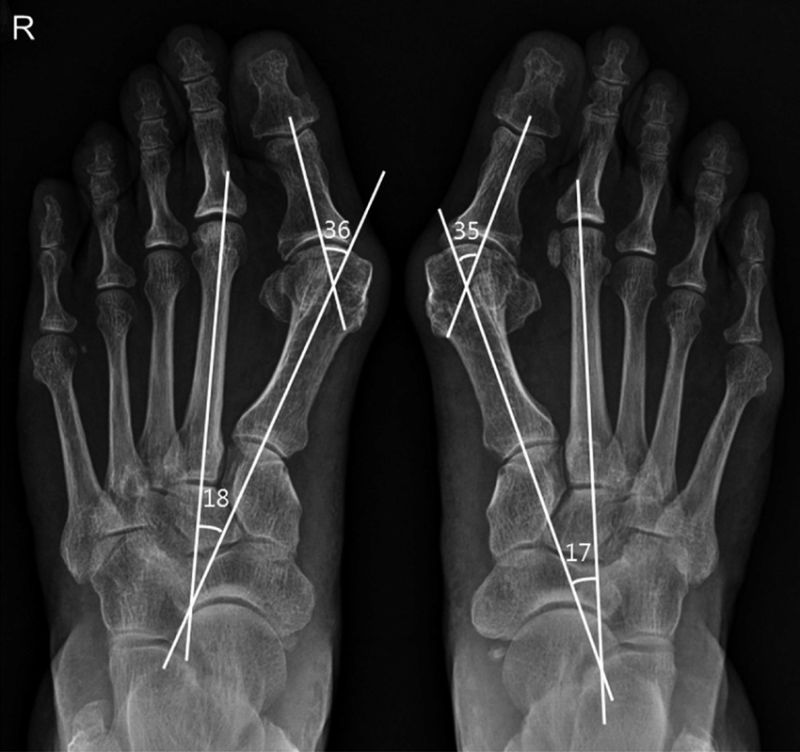

CURIOUS STUDY: Hallux Valgus Met I

SCARF: scarf osteotomy